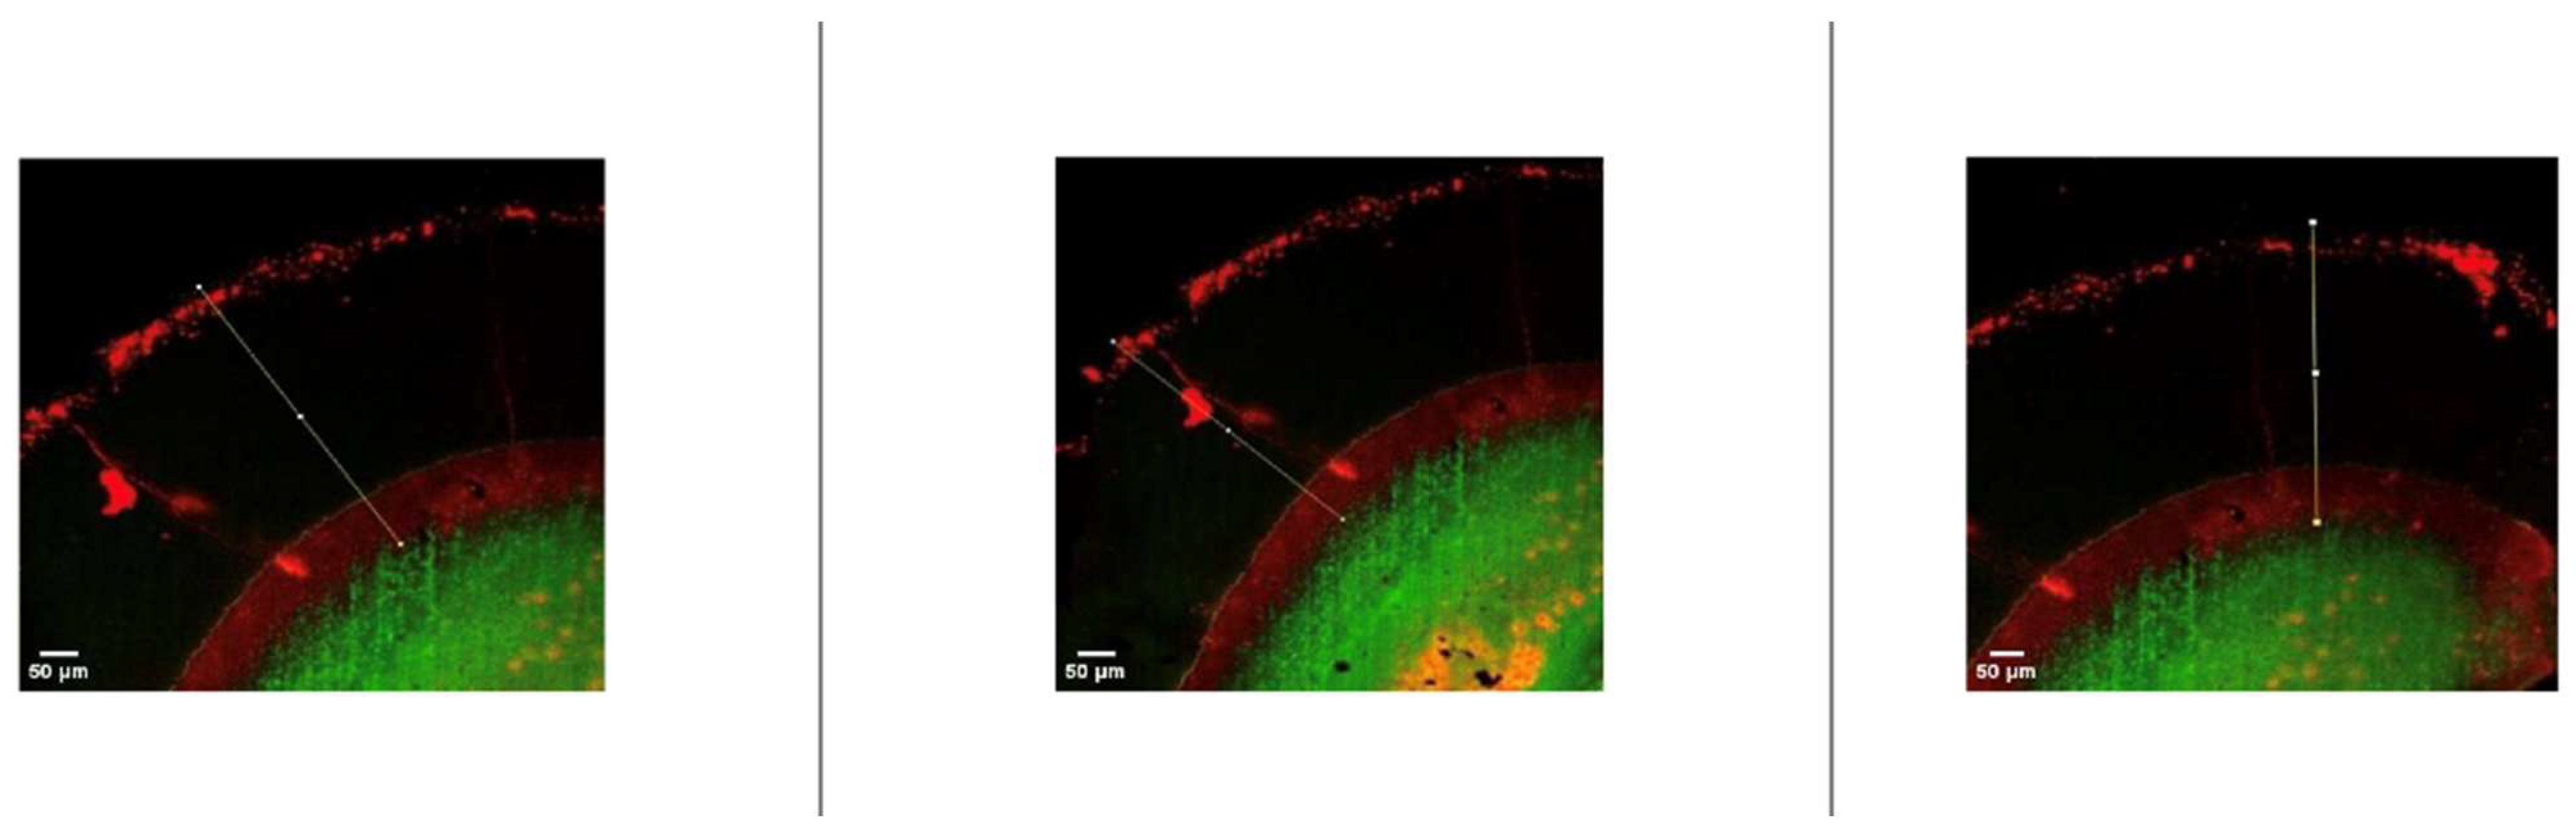

After resin infiltration, specimens were sectioned along the buccolingual plane using a water-cooled diamond saw. Resin penetration was assessed using a dual-fluorescence staining technique combined with confocal laser scanning microscopy (CLSM), as described by Paris et al. [21] Infiltrated regions were identified by red fluorescence, while non-infiltrated porous areas appeared green. Penetration depth was measured at three standardized locations per section using image analysis software, and mean values were calculated for statistical analysis.

Representative confocal laser scanning microscopy images illustrating resin penetration depths assessed using the dual-fluorescence staining technique are presented in Figure 3 and Figure 4.

Figure 3. Representative confocal laser scanning microscopy (CLSM) images showing resin penetration depth in experimental resin infiltration groups. Red fluorescence indicates infiltrated regions, whereas green fluorescence represents non-infiltrated porous enamel areas. White lines show the penetration depth of the resin infiltration.